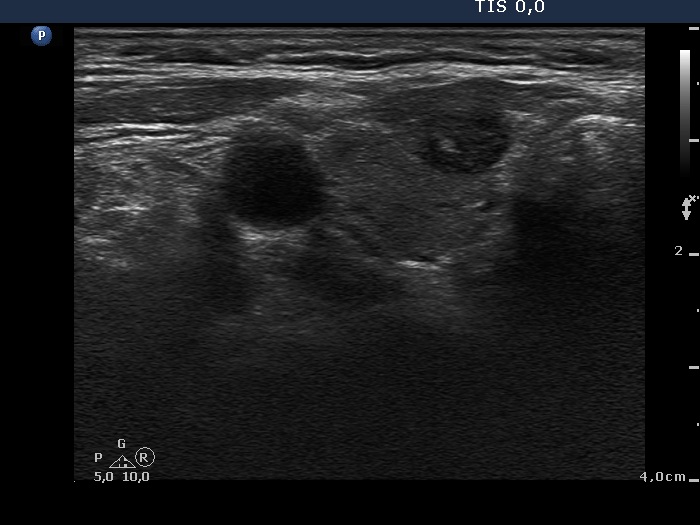

Ultrasonography. There was a hypoechogenic nodule presenting microcalcification in the ventromedial part of the right thyroid. According to the palpable mass in the right submandibular area a lymph node was found. The node did not presented hilum.